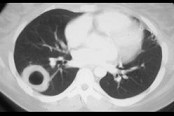

- 单项选择题男,45岁, 胸痛,咳嗽, 咳痰半月余,发热, 既往有副鼻窦炎病史,CT检查如图, 选择最可能的诊断 ( )

A、结节病

B、周围型肺癌

C、韦格肉芽肿

D、肺转移瘤

E、结核球